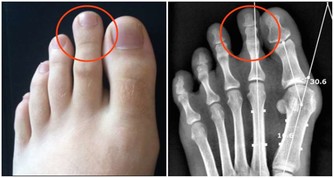

風濕科:動物內臟少吃

海鮮、啤酒、炒腰花、烤豬腰……你再這樣下去,醫生該拿什麼來救你?很多痛風患者的急性發作,都是因為吃!

動物內臟也是嘌呤含量較高的食物,所以風濕免疫科的醫生,會常重複這麼幾句話:低嘌呤飲食,少吃肉類、動物內臟、還有海鮮!

小貼士:痛風怎麼吃?

高嘌呤食物,高尿酸和痛風的人應該完全避免;

嘌呤食物,應該嚴格限量,在急性發作期不能食用;低嘌呤食物,可以放心食用。